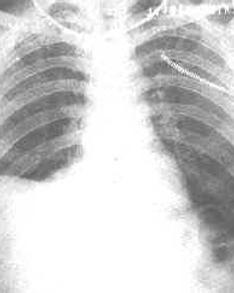

尽管目前许多强有力的抗生素在临床应用肺炎仍然是最常见的疾病之一在美国,肺炎伴胸腔积液位居胸腔积液病因的第2位渗出性胸腔积液病因的第1位。大多数类肺炎性胸腔积液通过有效的抗生素治疗而积液可以自行吸收。但是约10%的胸腔积液需要手术干预。[1]